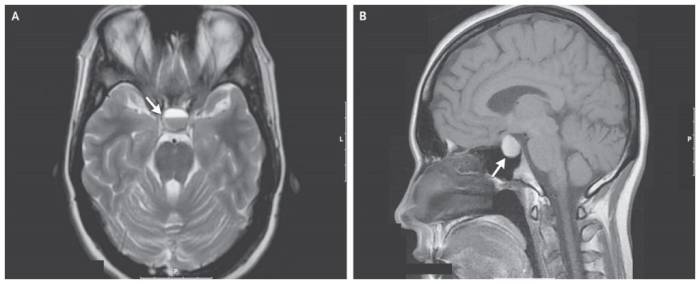

Чтобы исключить или подтвердить наличие рассматриваемого заболевания рекомендуется провести внутреннее исследование костной и мягкой ткани головного мозга посредством:

- Рентгенографического снимка кости черепа прямо и по бокам. В данном случае, симптомами наличия пролактиномы будет увеличение объема и трансформация формы самого турецкого седла;

- Компьютерной томографии, позволяющей оценить степень разрушения кости черепа;

- Магнитно-резонансной томографии (МРТ) при повышенном пролактине, с использованием контрастного вещества для более детального изучения структуры аденомы гипофиза и ее разрастания;